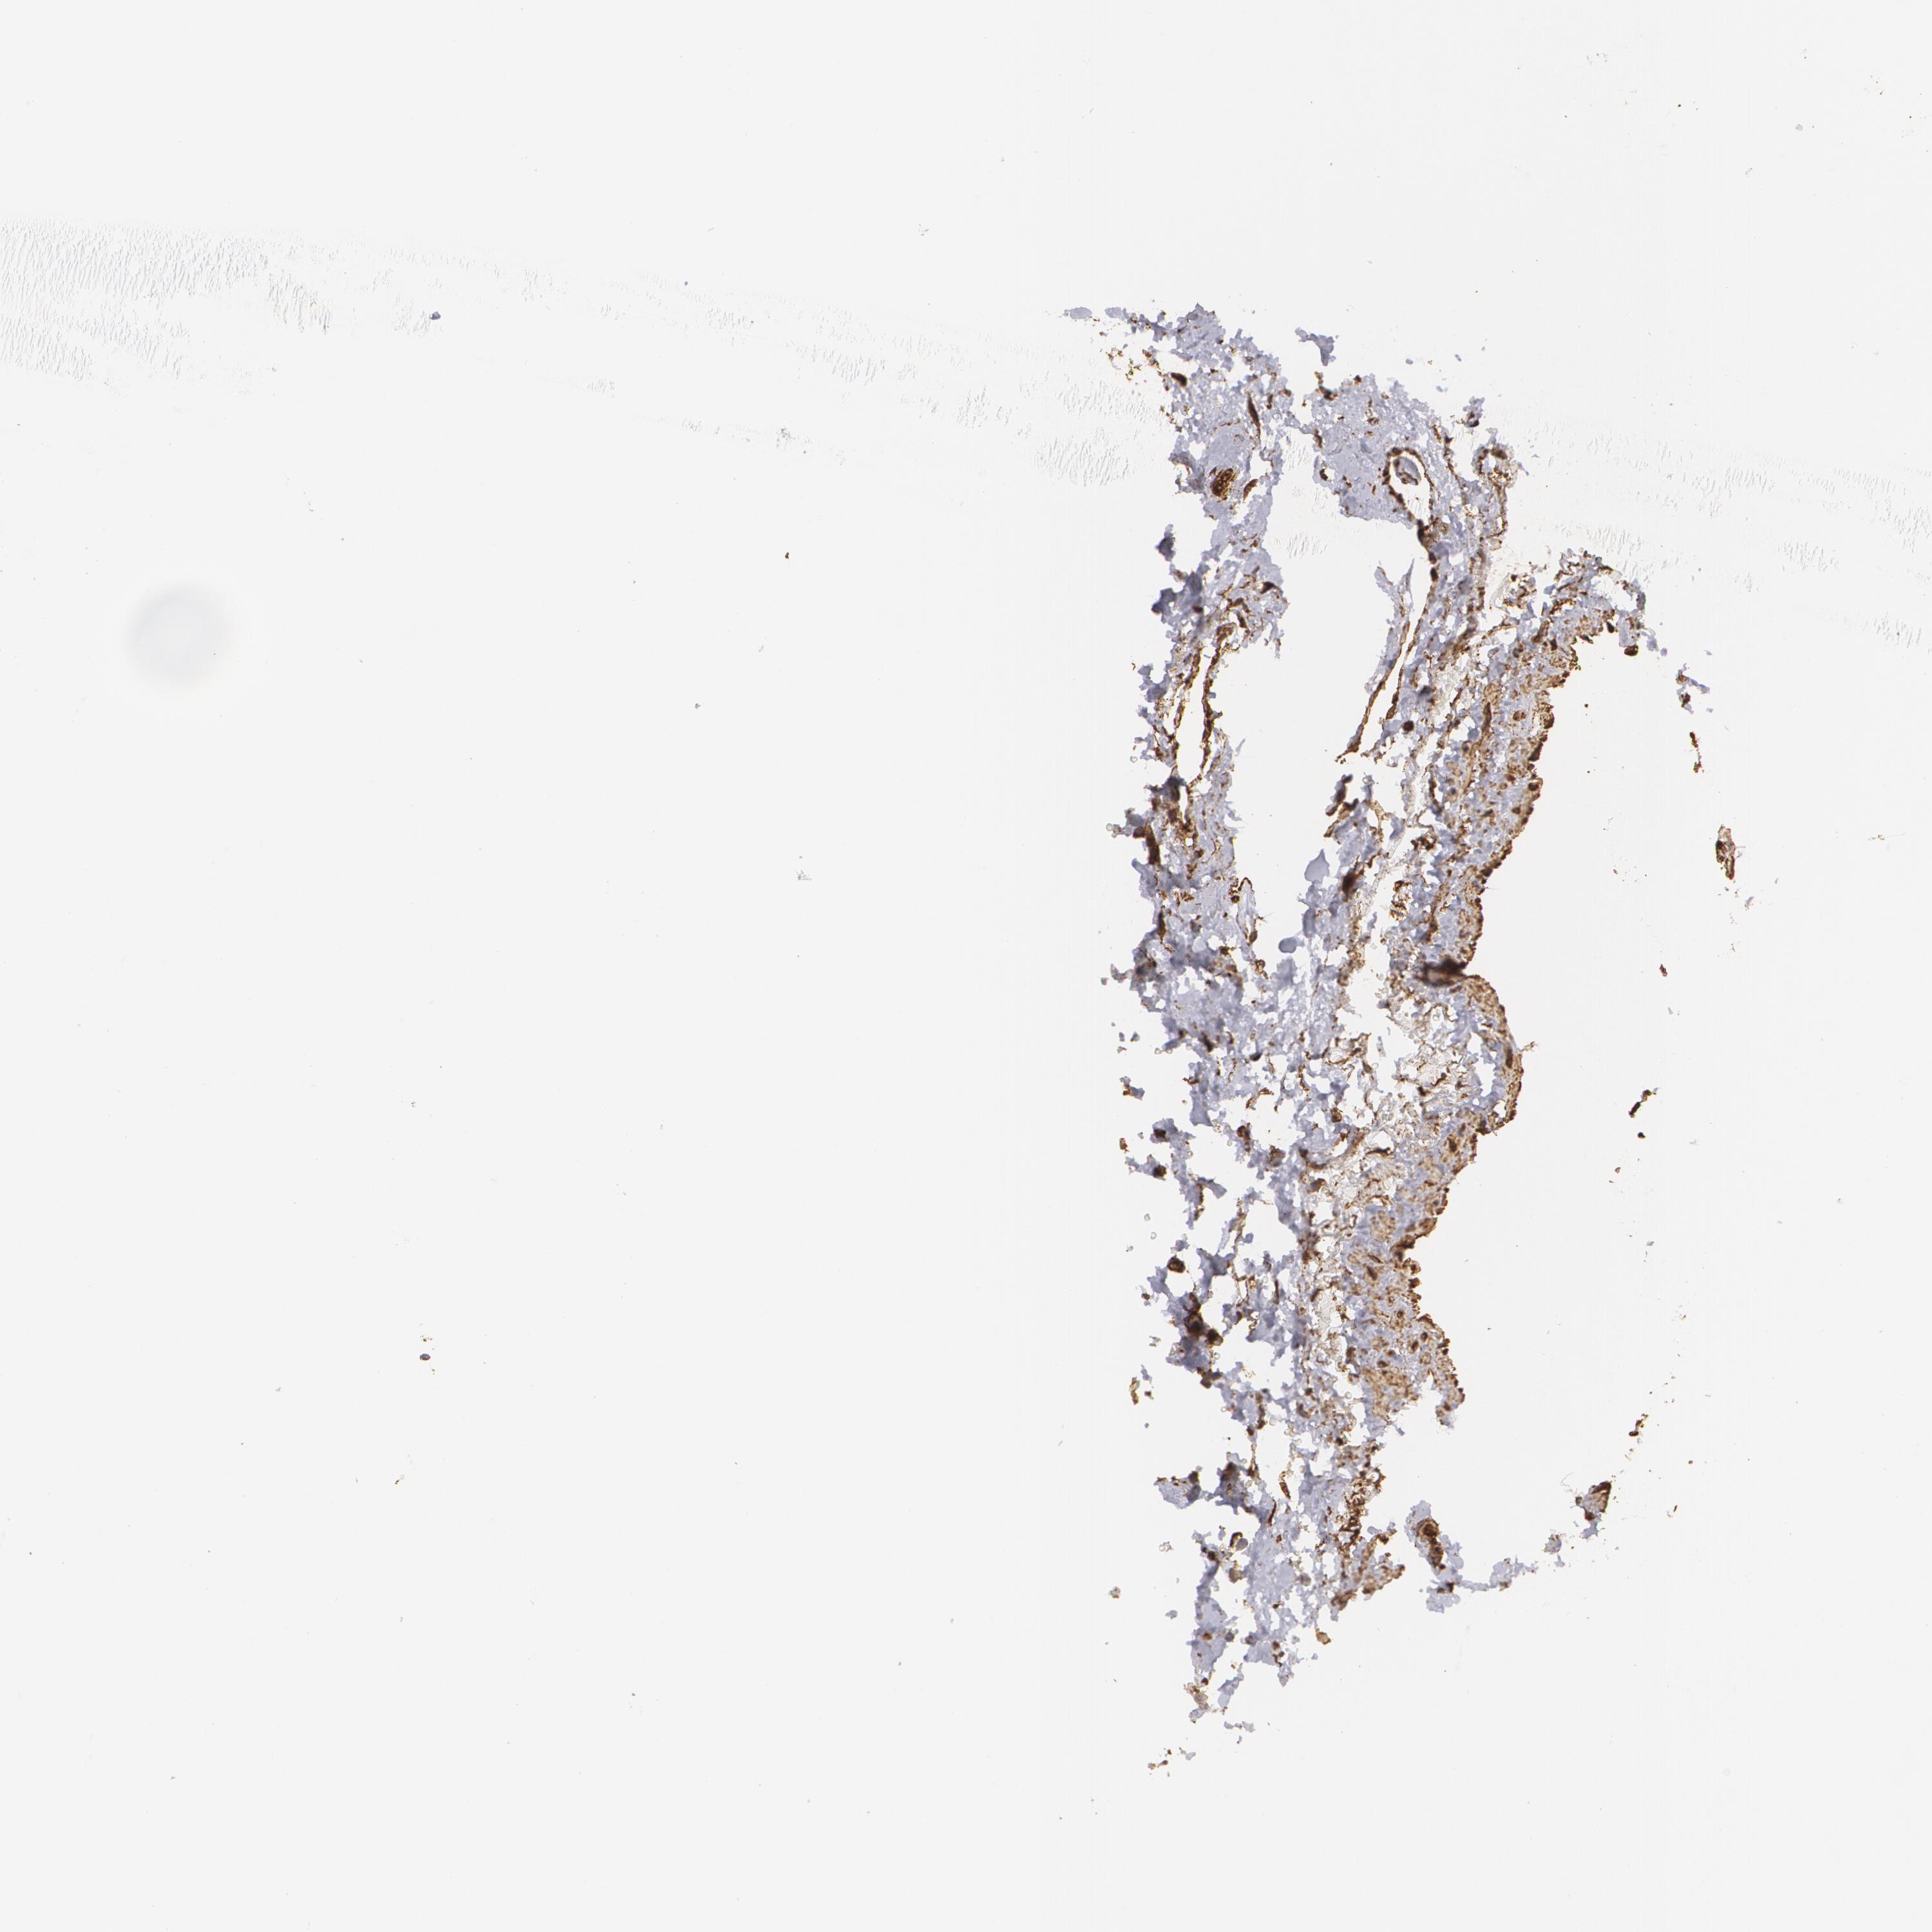

BRCA TCGA BRCA VALIDATION PROTEIN EXPRESSION

ANTIBODIES

AND

VALIDATION